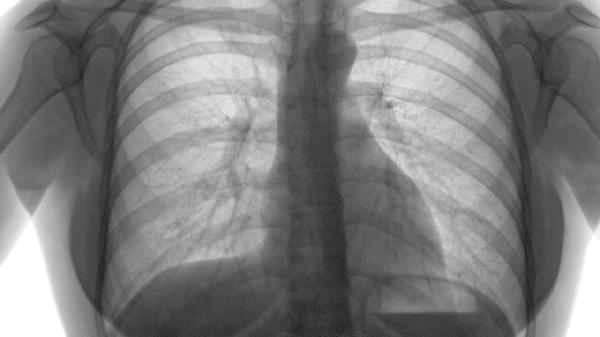

肺气肿可通过支气管扩张剂、糖皮质激素、祛痰药、抗生素、抗氧化剂等药物治疗。肺气肿通常由长期吸烟、空气污染、职业粉尘暴露、遗传因素、反复呼吸道感染等原因引起。